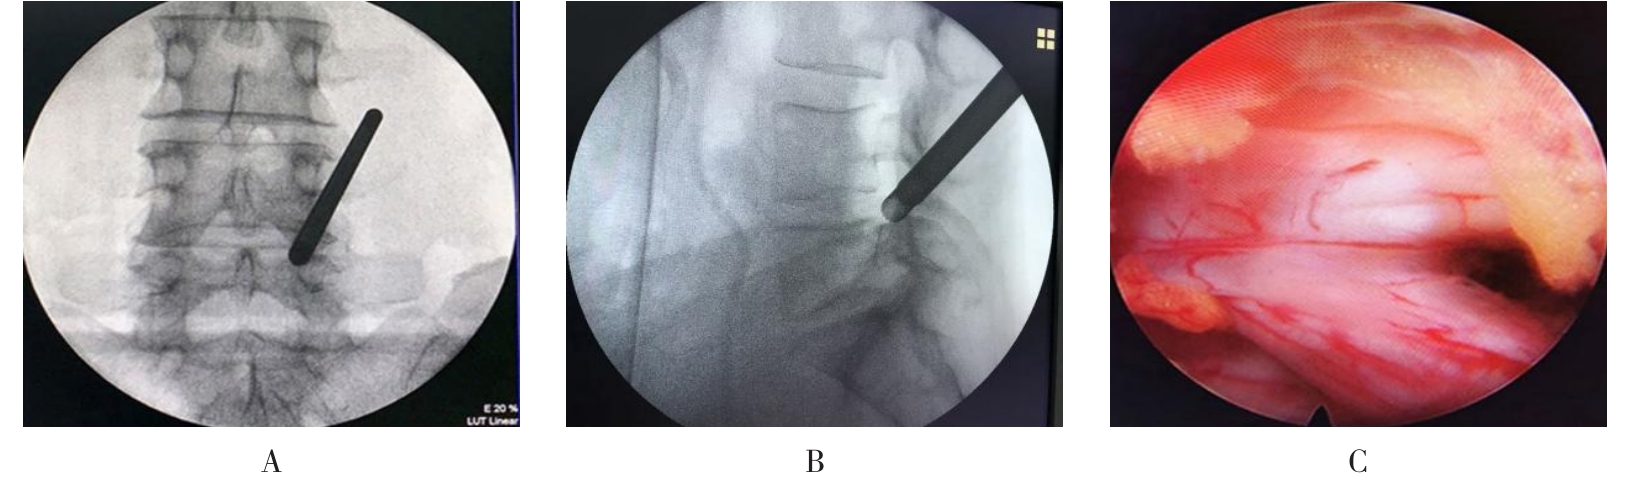

• 不同入路脊柱内镜手术治疗L4/5节段脱垂型腰椎间盘突出症的疗效比较

摘要:目的 观察经椎间孔入路内镜下腰椎间盘切除术(TELD)和经椎板间入路内镜下腰椎间盘摘除术(IELD)治疗L4/5节段脱垂型腰椎间盘突出症(LDH)的临床疗效。方法 回顾性分析2020年11月-2022年11月该院采用脊柱内镜手术治疗的75例L4/5节段脱垂型LDH患者的临床资料。根据手术入路的不同,将患者分为TELD组(53例)和IELD组(22例)。比较两组患者的手术情况和术后疗效。结果 与TELD组比较,IELD组的手术时间明显缩短,术中透视次数明显减少,差异均有统计学意义(P < 0.05);两组患者住院时间和并发症发生率比较,差异均无统计学意义(P > 0.05)。所有患者术后均获得12~19个月的随访。两组患者末次随访时的视觉模拟评分法(VAS)评分和Oswestry功能障碍指数(ODI)明显低于术前,且IELD组明显低于TELD组,差异均有统计学意义(P < 0.05)。按照突出物和神经根的不同位置进一步分析,两组肩上型患者(TELD组10例,IELD组6例)末次随访时的VAS评分和ODI明显低于术前,且IELD组末次随访时的VAS评分明显低于TELD组,差异均有统计学意义(P < 0.05);两组腋下型患者(TELD组8例,IELD组16例)末次随访时的VAS评分和ODI明显低于术前,且IELD组明显低于TELD组,差异均有统计学意义(P < 0.05);35例肩前型患者经TELD术后,末次随访时的VAS评分和ODI明显低于术前,差异有统计学意义(P < 0.05)。按照突出物的不同Lee分区进一步分析,两组Lee Ⅲ区患者(TELD组44例,IELD组10例)末次随访时的VAS评分和ODI明显低于术前,且IELD组的ODI明显低于TELD组,差异均有统计学意义(P < 0.05);两组Lee Ⅳ区患者(TELD组9例,IELD组12例)末次随访时的VAS评分和ODI明显低于术前,且IELD组明显低于TELD组,差异均有统计学意义(P < 0.05)。结论 采用TELD和IELD治疗L4/5节段脱垂型LDH,均可获得较满意的减压效果,但IELD的手术时间相对较短,X线透视次数较少,且对肩上型、腋下型、Lee Ⅲ区和Lee Ⅳ区的减压效果更有优势。